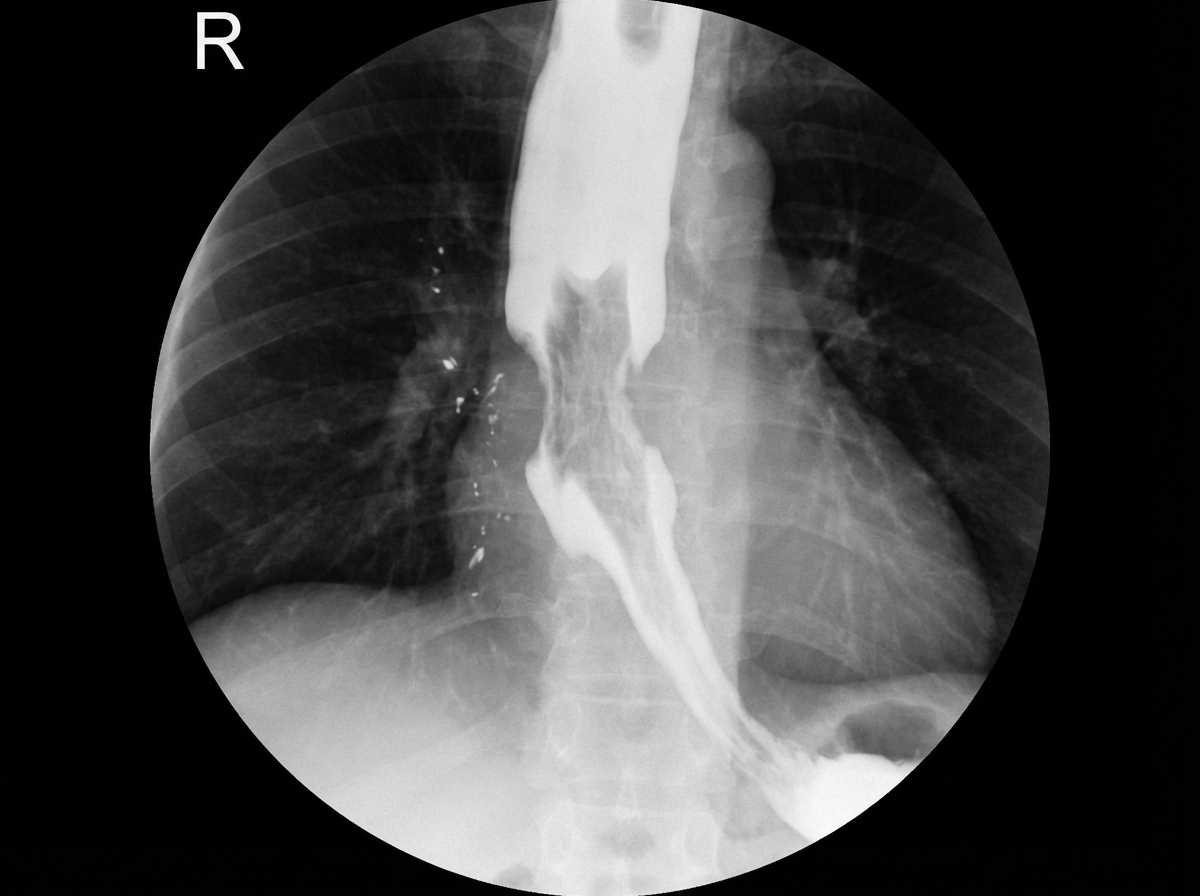

What is the diagnosis suggested by the barium X-ray findings?

Explanation: ***Carcinoma of the esophagus*** - Classic barium swallow findings include **irregular filling defect**, **shouldering**, and **mucosal destruction** with an **apple-core or rat-tail appearance**. - Shows **abrupt transition** from normal to abnormal mucosa, indicating **malignant stricture** with tissue destruction. *Achalasia* - Barium swallow demonstrates **smooth, symmetric bird-beak tapering** at the gastroesophageal junction without mucosal irregularity. - Shows **retained contrast** in a dilated esophagus due to **failure of lower esophageal sphincter relaxation**. *Plummer-Vinson Syndrome* - Characterized by a **smooth, thin postcricoid web** in the upper esophagus on barium swallow. - Associated with **iron deficiency anemia** and typically affects the **cervical esophagus**, not causing irregular filling defects. *Gastroesophageal reflux disease (GERD)* - Barium swallow may show **reflux of contrast** into the esophagus during fluoroscopy but **no structural lesion**. - May demonstrate **hiatal hernia** or **esophagitis** but lacks the irregular filling defect seen in malignancy.